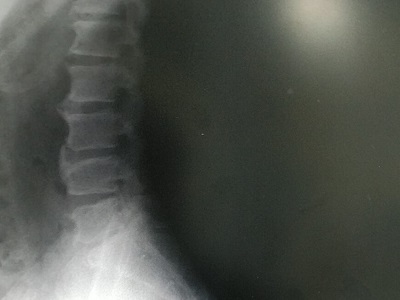

ぎっくり背中というよりは、危うく帰ってきた椎間板ヘルニアに陥るところでした。

今回はまだ椎間板はやられていないようなので、安堵っちゃー安堵なんですけど、それだから痛み止めと湿布薬しか処方されないので、爆弾抱えたままってやつには変わりないよねえ。